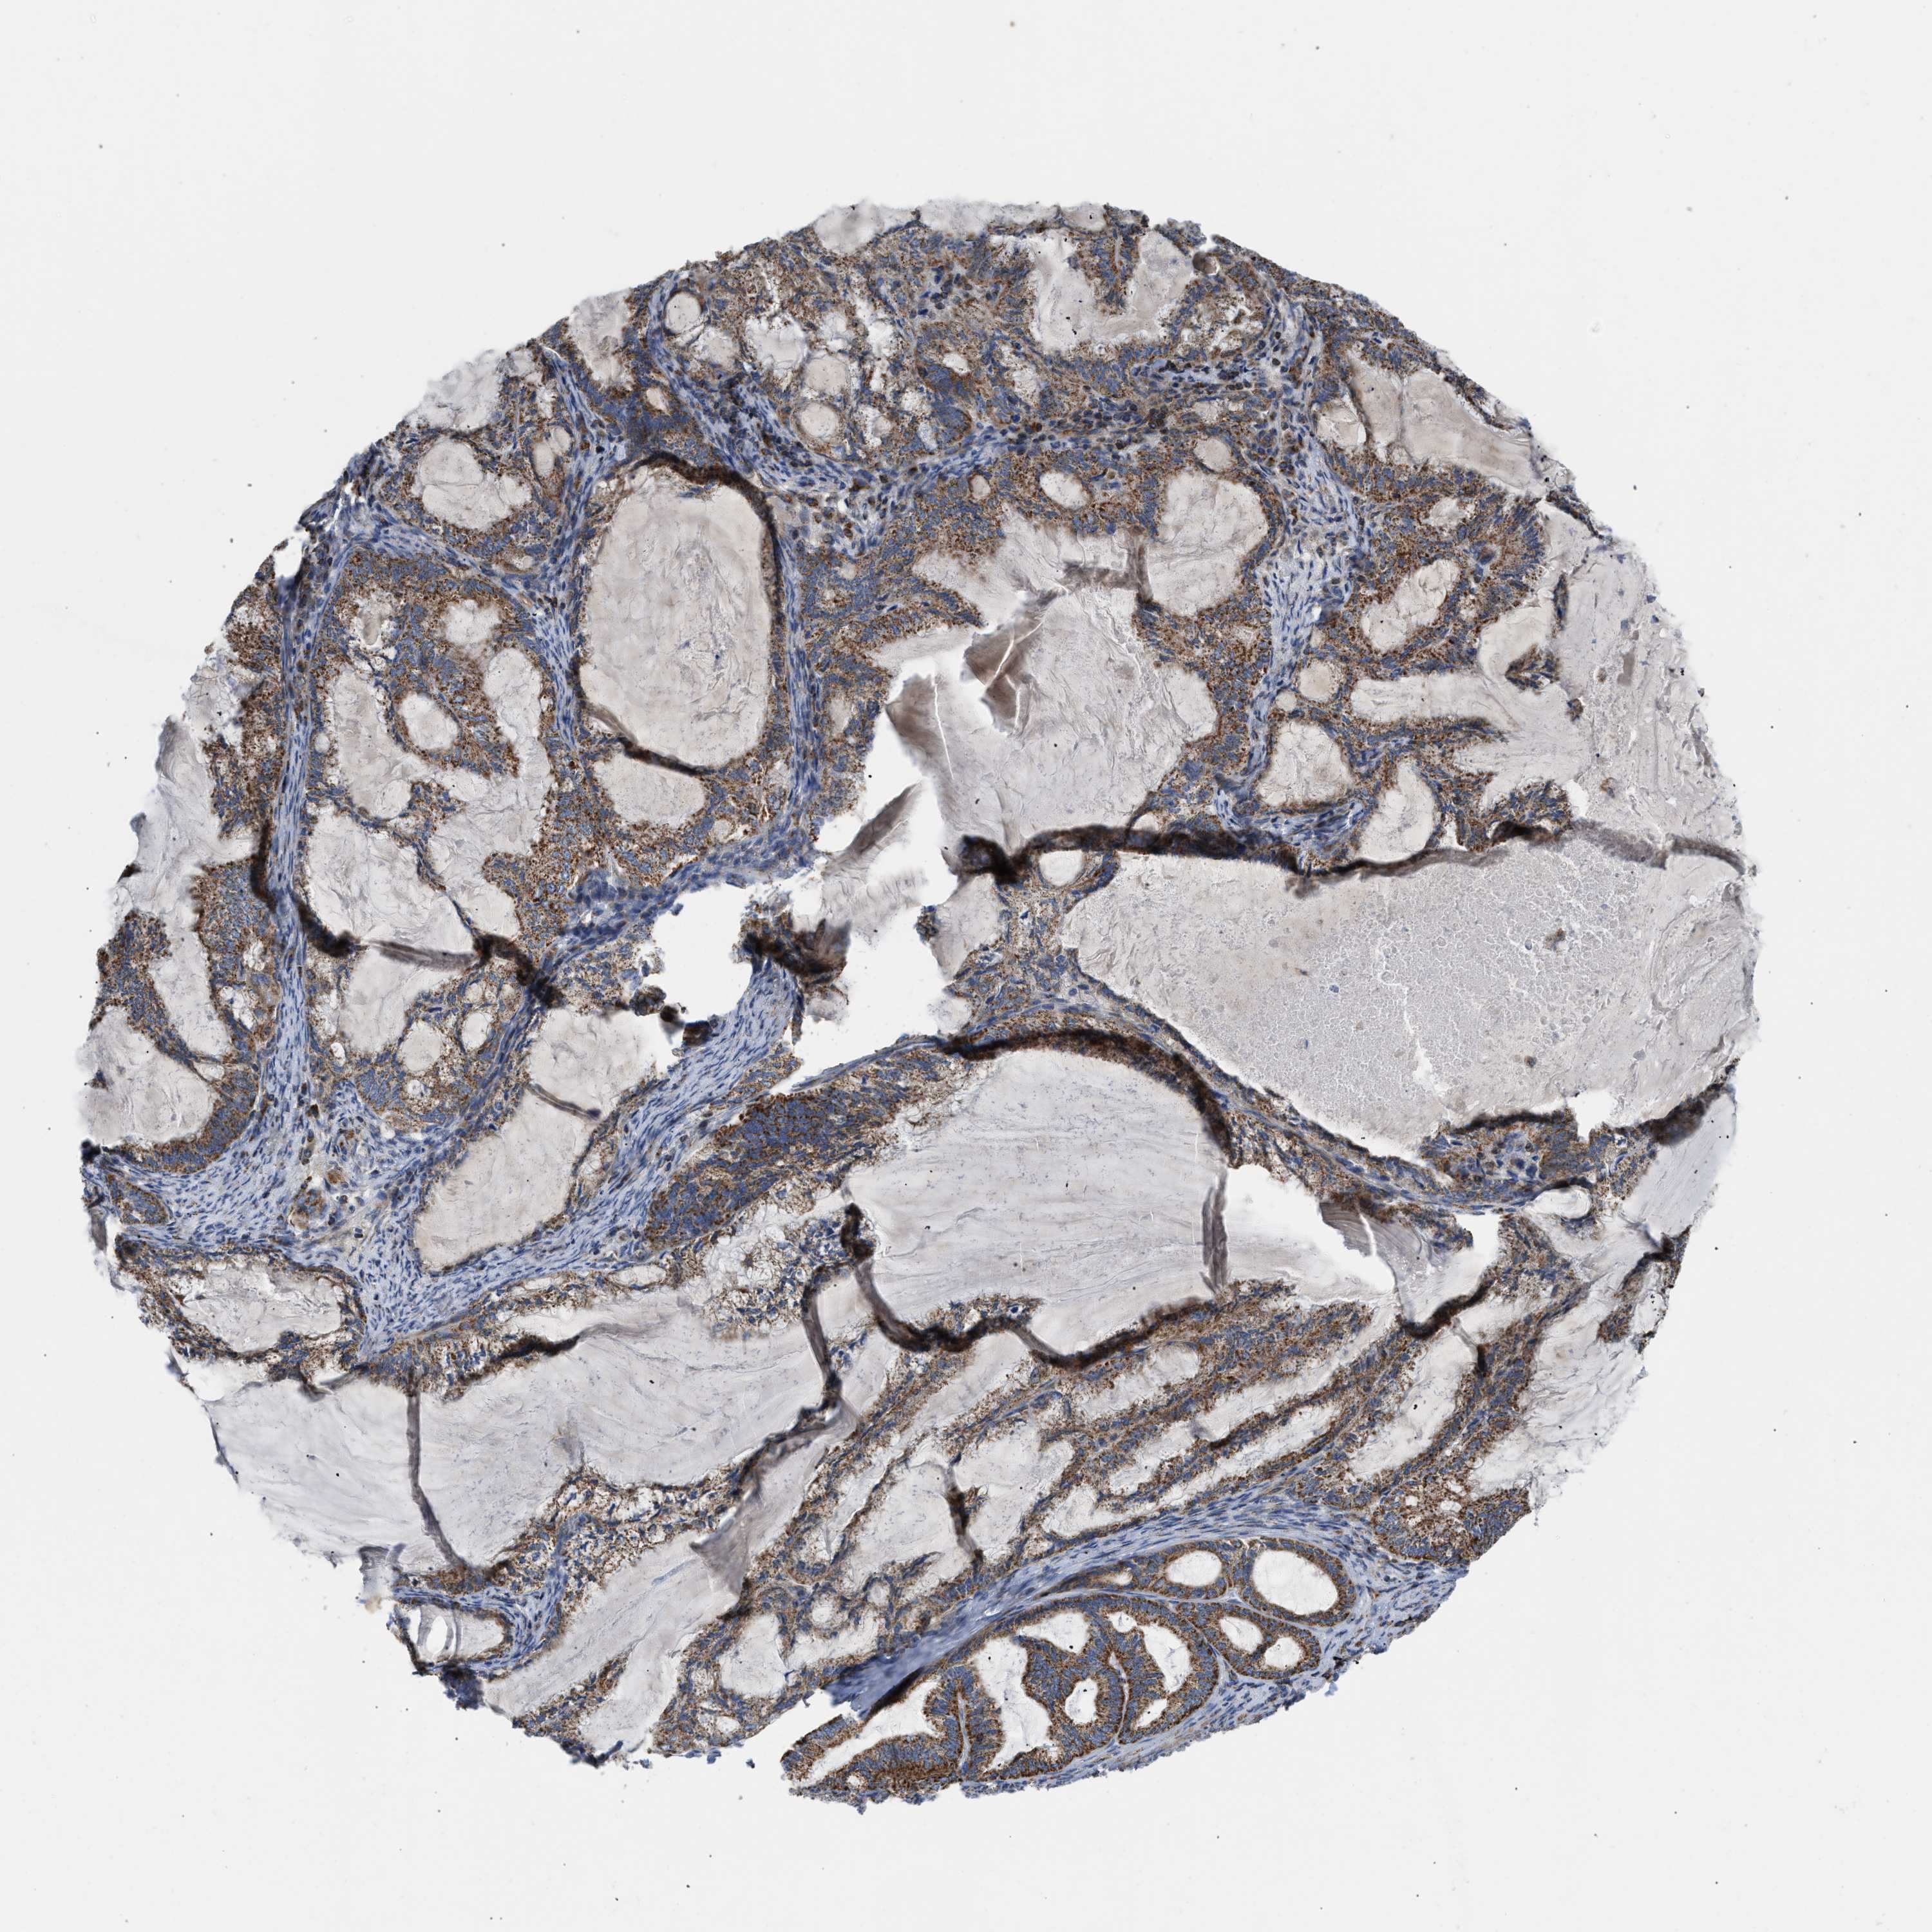

ENDOMETRIAL CANCER - Protein expressioni

A mouse-over function shows sample information and annotation data. Click on an image to view it in a full screen mode. Samples can be filtered based on level of antibody staining by selecting one or several of the following categories: high, medium, low and not detected. The assay and annotation is described here.

Note that samples used for immunohistochemistry by the Human Protein Atlas do not correspond to samples in the TCGA dataset.

Antibody stainingi

Antibody staining in the annotated cell types in the current human tissue is reported as not detected, low, medium, or high, based on conventional immunohistochemistry profiling in selected tissues. This score is based on the combination of the staining intensity and fraction of stained cells.

Each image is clickable and will lead to virtual microscopy that enables deeper exploration of all samples and also displays staining intensity scores, fraction scores and subcellular localization as well as patient and tissue information for each sample.

Antibody HPA003279

Antibody HPA003360

Antibody CAB019303

Staining

High

Medium

Low

Not detected

Intensity

Strong

Moderate

Weak

Negative

Quantity

>75%

75%-25%

<25%

None

Location

Nuclear

Cytoplasmic/membranous

Cytoplasmic/membranous,nuclear